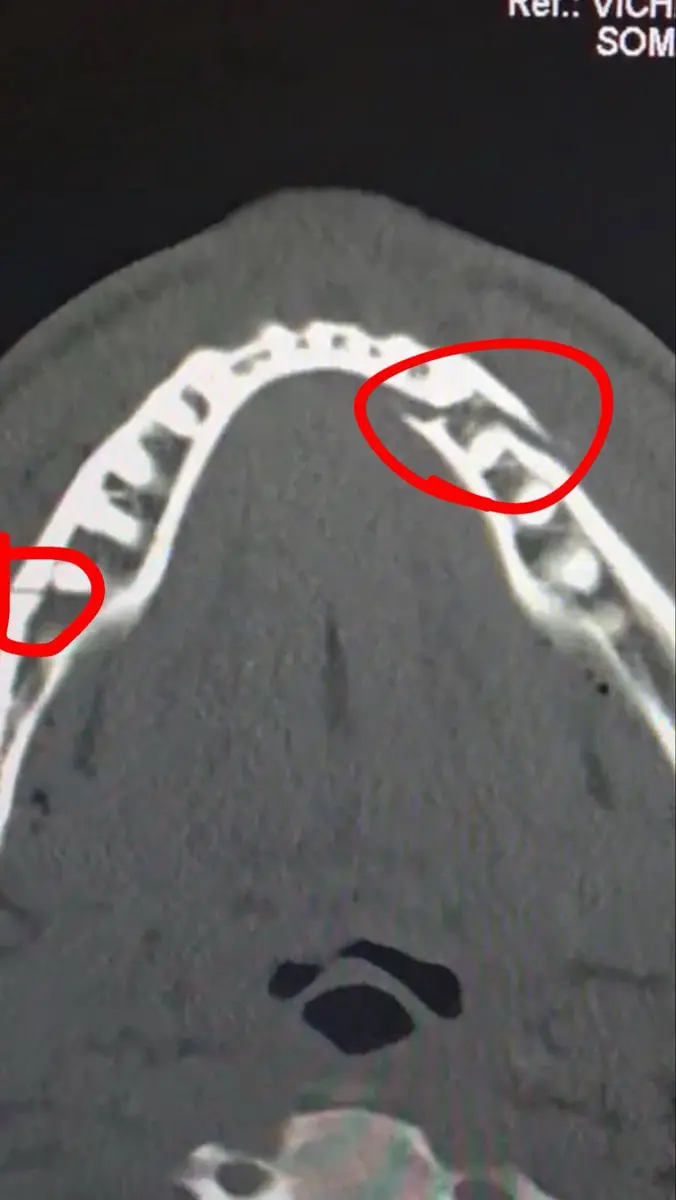

در این مبارزه، جاشوا در راندهای پنجم و ششم دو بار پاول را نقش زمین کرد و در نهایت بوکسور آمریکایی نتوانست پیش از پایان شمارش داور به مبارزه بازگردد. پاول پس از این شکست، تصویری از عکس رادیولوژی فک خود را در شبکه اجتماعی «ایکس» منتشر کرد و نوشت: «شکست از دو ناحیه در فک. ده روز دیگر کانلو(بوکسور حرفهای مکزیکی) را به من بدهید.»

به گزارش ایلنا، جیک پاول با تأیید مصدومیت شدید خود، اعلام کرد در جریان شکست برابر آنتونی جاشوا فکش در دو نقطه دچار شکستگی شده است. این دو بوکسور در مبارزهای در وزن سنگین در شهر میامی آمریکا به مصاف هم رفتند و این دیدار در نهایت با برتری قاطع ستاره انگلیسی به پایان رسید.